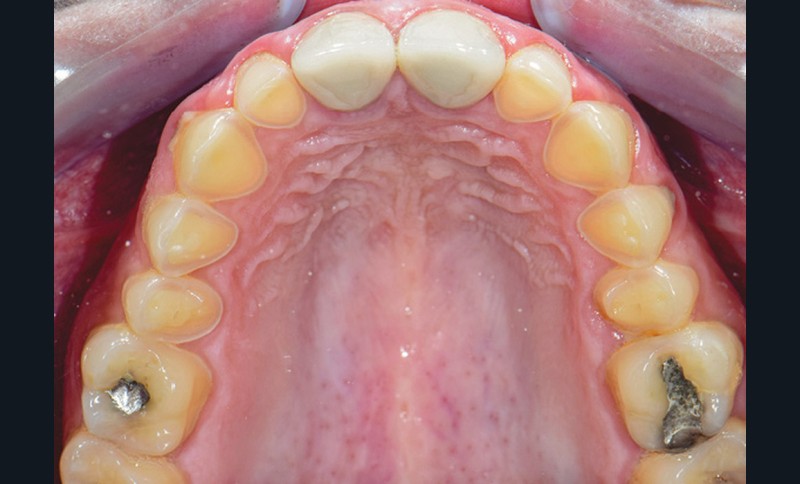

L’arcade maxillaire présente des signes d’usure érosive caractéristiques d’attaques acides : surface lisse, de couleur satinée, présence d’un pourtour d’émail sain en regard du sulcus, et effacement des morphologies dentaires telles que la disparition des cuspides palatines des prémolaires et de la 16. En revanche, 26 et 46 ne présentent aucun problème d’usure. La patiente ne rapporte pas de signes d’hyperesthésie dentinaire. Par ailleurs, la dimension verticale d’occlusion (DVO) étant conservée, la patiente présente une usure majeure compensée par l’égression dentaire (ce qui montre une évolutivité lente).